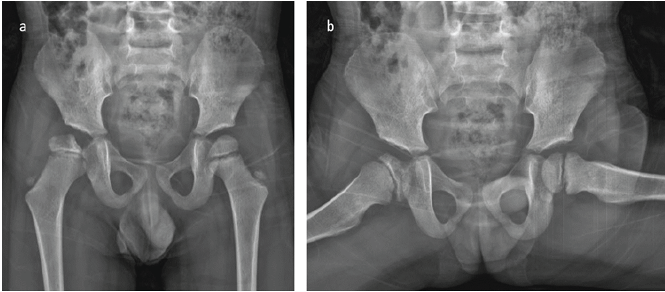

The patient was treated and followed for a total of 17 days in the hospital. Follow-up hematologic testing demonstrated negative Factor VIII inhibitor assays on two separate occasions, together with normal levels of VWF and Factor IX, fully supporting the diagnosis of Hemophilia A without inhibitor development. Following confirmation of hemophilia and satisfactory blood test results, he was discharged with detailed recommendations for the use of the Pavlik harness and instructions for follow-up at the outpatient clinic, along with a prescription to continue the 250 units of factor VIII. The Pavlik harness was utilized for a total duration of 12 weeks, during which the patient’s right hip demonstrated a full range of motion and no pain. A control ultrasound at the end of treatment showed a normal appearance of the hip joint. The patient continued to be followed up at 6-month intervals for potential femoral head avascular necrosis (AVN) or acetabular dysplasia. Throughout this follow-up period, the patient’s records did not document any significant spontaneous joint bleeding episodes; however, he did experience occasional transient joint pain episodes, which were successfully managed with factor VIII treatment. Three years post-operatively, a follow-up X-ray revealed irregularity proximal femoral epiphysis, characterized by a narrowed lateral pillar that retained over 50% of its height. The acetabular roof appeared normal, as indicated by an acceptable acetabular index (AI); however, irregularities were observed on the acetabular joint surface (Fig. 3f). A follow-up MRI, utilizing T2-weighted coronal images obtained at 3 years post-operation, demonstrated a cystic lesion accompanied by a surrounding hyperintense signal on the T1-weighted coronal images. These findings are suggestive of hemophilic arthropathy, specifically a subchondral cyst formed due to recurrent intra-articular hemorrhages (Fig. 3c, d, e). The X-ray taken in the 4th post-operative year illustrated concentric reduction of the femur along with flattening and remodeling of the femoral head. Furthermore, a slight steepening of the acetabulum was observed relative to both the contralateral hip and the imaging from the previous year. These findings are consistent with Catterall Grade 3 or Salter-Thompson Type 2b AVN (Fig. 4).

Figure 4: (a and b) X-ray at the 4th post-operative year showing concentric reduction of the femur with flattening and remodeling of the femoral head. Note the slight steepening of the acetabulum compared to the contralateral hip and the previous year. The findings resemble Catterall Grade 3 or Salter-Thompson Type 2b avascular necrosis.